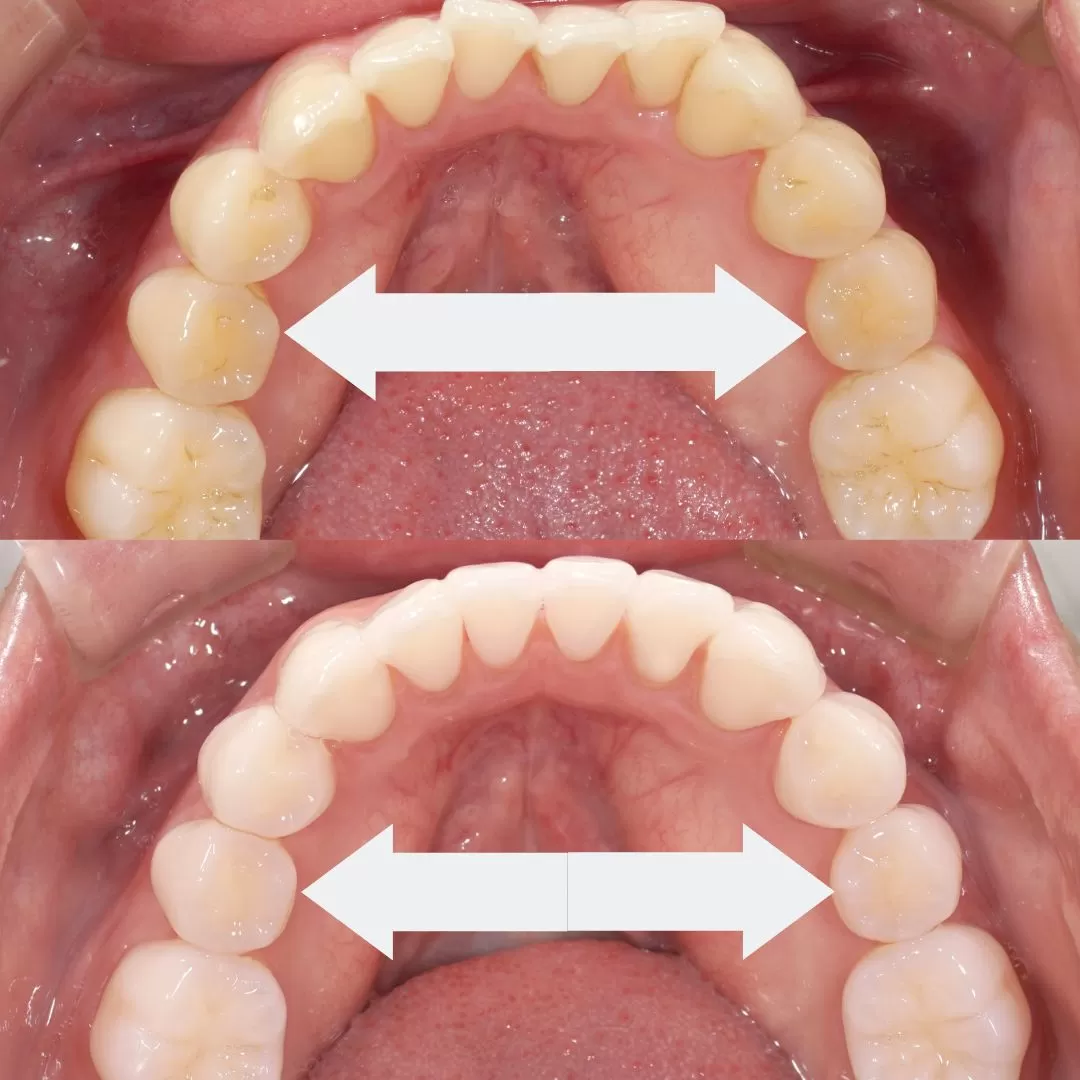

これが拡大です。

拡大は本来あるべき歯の位置と歯の噛み合わせに歯が無理なく

いきますので、

顎の位置すら変えます。

そもそも奥歯の幅径がせまいから

【前歯がでるのです。】

出っ歯は奥歯が作り出す、奥歯の幅径が狭いから、そして

その結果、奥歯の高さを失い、下の顎が後ろへ。

この奥歯の幅径が大事。特にマウスピース矯正はこれを利用して行う矯正。

では模型を見てみましょう

【拡大】ということをしています。

歯の軸を起こしましてスペースを作るのです。

奥歯の噛み合わせの位置が変わるので、奥からの治療となり

全体での歯列矯正となります。

このように拡大する歯列矯正には良いことがたくさんあります。